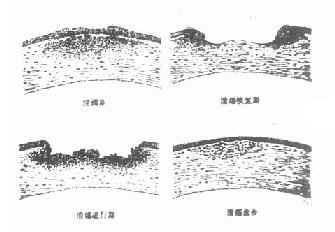

(三)恢复期即炎症的转归阶段。经过治疗,溃疡可逐渐转向清洁,周围健康角膜上皮细胞迅速生长,将溃疡面完全覆盖,在角膜上皮细胞的掩盖下,角膜基质的成纤维细胞增生和合成的新胶原,修补基质的缺损处,角膜溃疡遂告痊愈。角膜中央区溃疡愈合方式多为无新生血管性愈合;周边部溃疡多为有血管愈合。新形成的角膜基质胶原纤维排列紊乱,构成了不透明的瘢痕组织。位于中央区的致密瘢痕可使患眼视力严重丧失。浅层溃疡,仅有角膜上皮层覆盖创面,无结缔组织增生者,则在损伤处形成透明的小凹面,荧光素不染色,称为角膜小面(corneal facet)。(图6-1,6-2)

1.角膜云翳(cornealnebual)薄云雾状的角膜瘢痕。用斜照法或裂隙灯检查方法可发现。

2.角膜斑翳(cornealmacula)较厚,呈灰白色混浊,半透明,肉眼即可看见。

3.角膜白斑(cornelleucoma )为最厚的角膜瘢痕,呈乳白色或瓷白色混浊,不透明,一望而知。